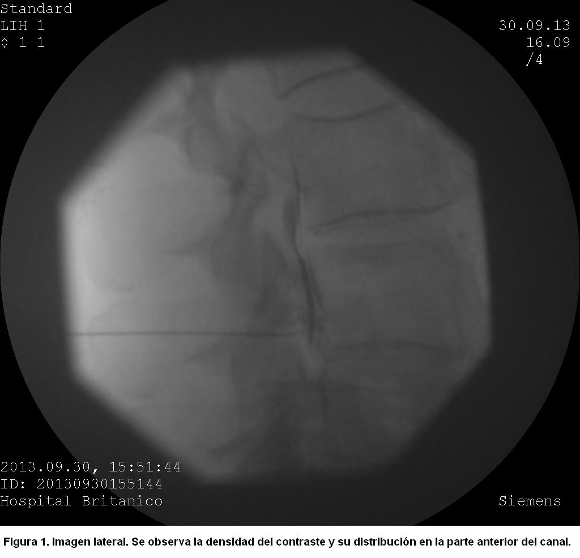

Al inyectar con igual técnica 0.5 ml de contraste a nivel del foramen L4, se observó en el enfoque lateral una densa imagen linear y homogénea concentrada en la parte anterior del canal espinal, que se extendía por encima del foramen del cuerpo vertebral superior (figura 1).